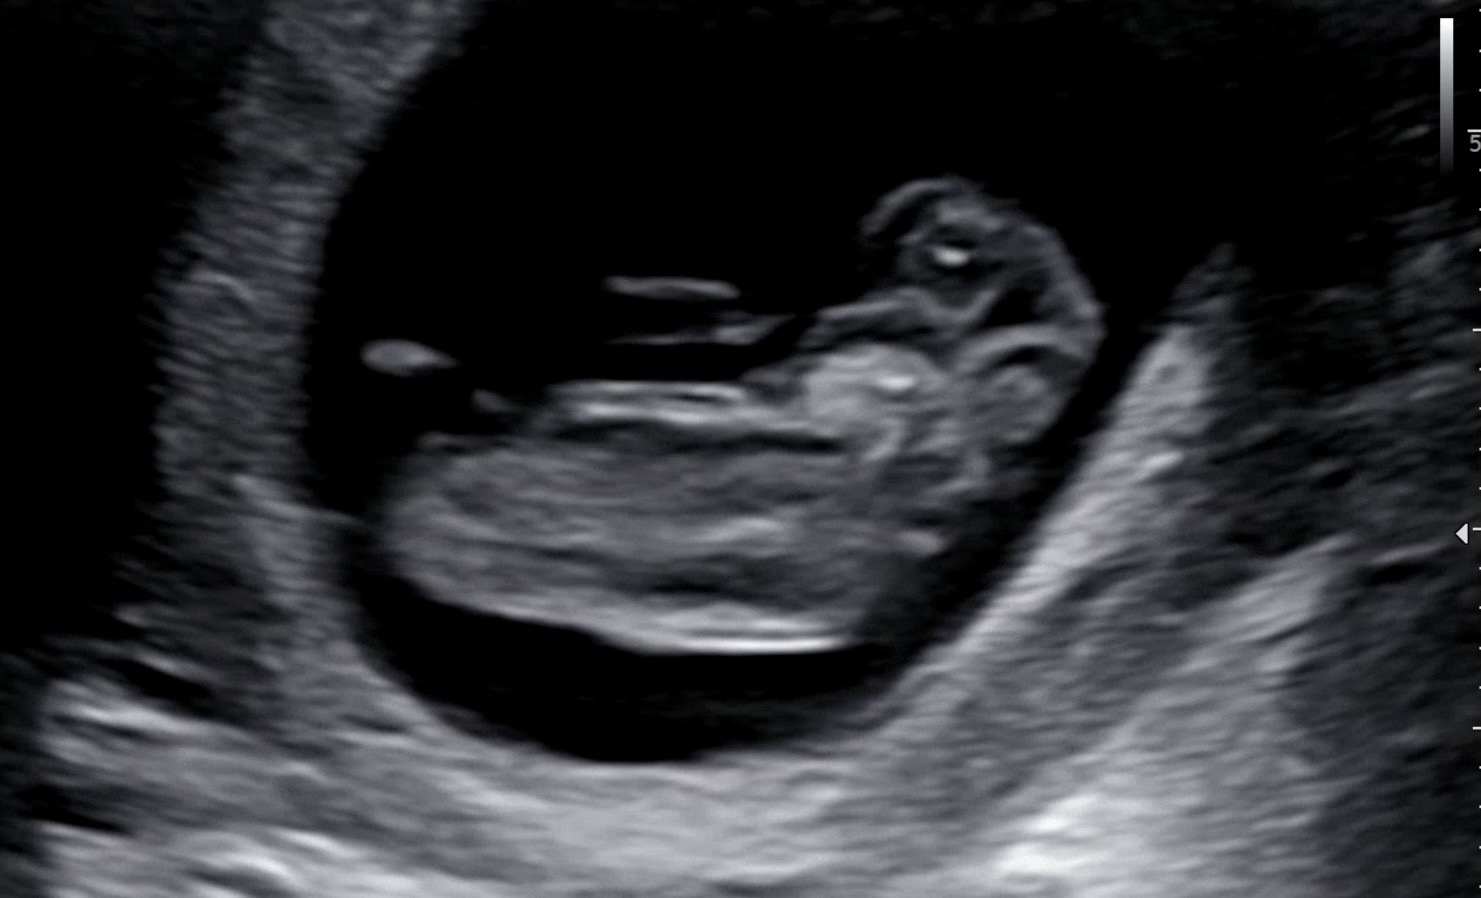

딸일까용? 아들일까용? (10주차)

베이비빌리 각도법AI 해보니까 68%딸이라고 하긴 하는데 너무너무 궁금해서 남겨봅니다!! 10주차에용!!